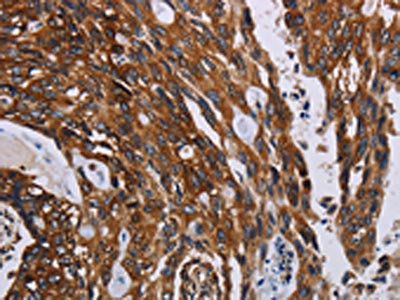

The image on the left is immunohistochemistry of paraffin-embedded Human colon cancer tissue using CSB-PA163096(KARS Antibody) at dilution 1/60, on the right is treated with fusion protein. (Original magnification: ×200)